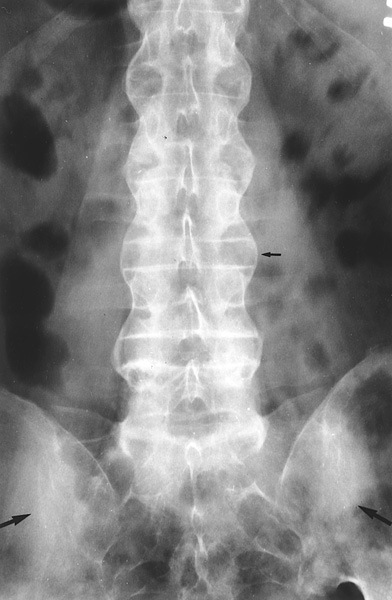

Рентгенограмма позвоночного столба при болезни Бехтерева